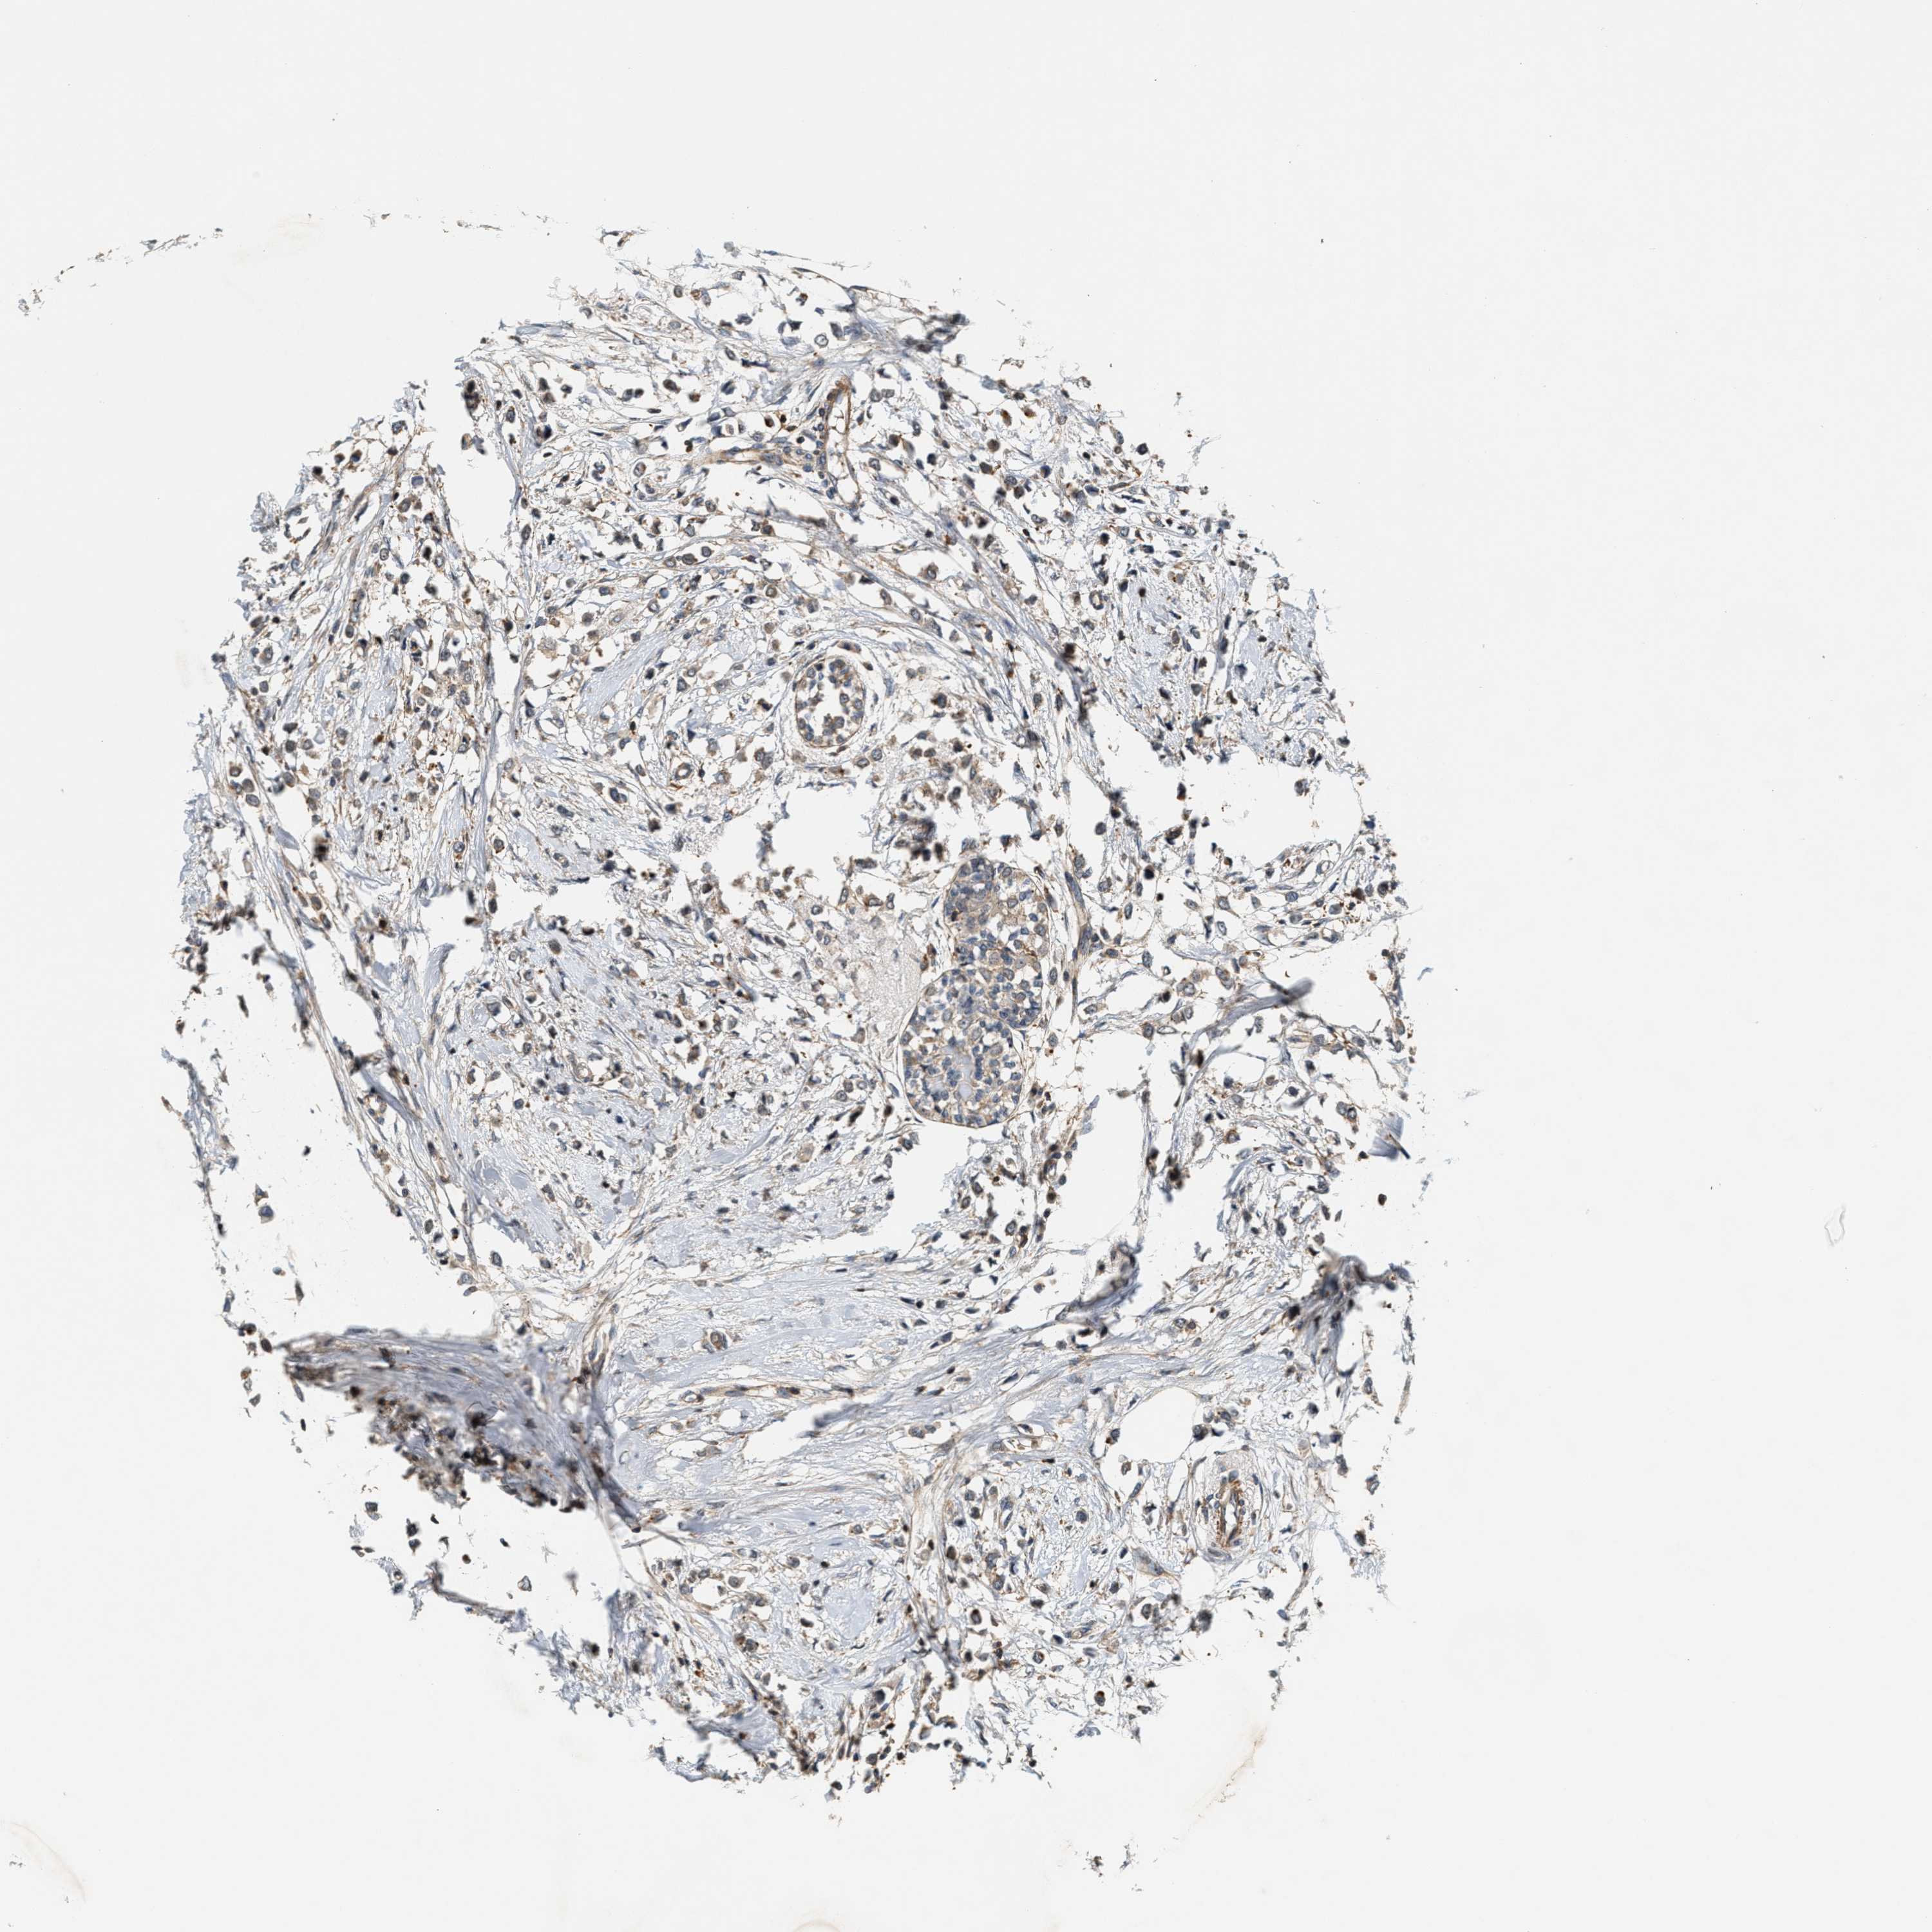

CANCER BREAST CANCER Show tissue menu

BRCA TCGA BRCA VALIDATION PROTEIN EXPRESSION

ANTIBODIES

AND

VALIDATION